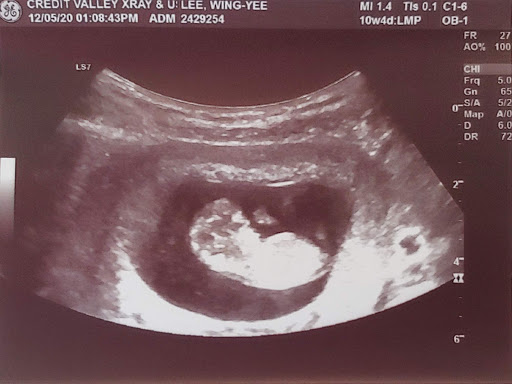

Yes, we have anecdotal evidence that the COVID-19 lockdown has started a baby boom! Renee and I are pleased to introduce Baby No. 6! Amelia is now two and a half years old so we're definitely overdue! LOL! This time, we're really going to fill the Odyssey and there will not be any spots for the grandparents! ðŸ˜

The kids are very thrilled with the news and couldn't wait to tell their friends. The oldest two are praying for a little brother and the younger three are hoping for a baby girl. We do think it'd be nice for Athan to finally have a brother, and we are running out of "A" girl names as well! 😜

Baby's due date will be early December and I'm really hoping the pandemic will be over by then. I really wish I will be allowed to accompany Renee during and after the delivery in the hospital. All of our kids were on the light side and had to stay in the hospital for a couple of nights. So, it'd be good to be able to be there with Renee and baby. Please keep us in your prayers!